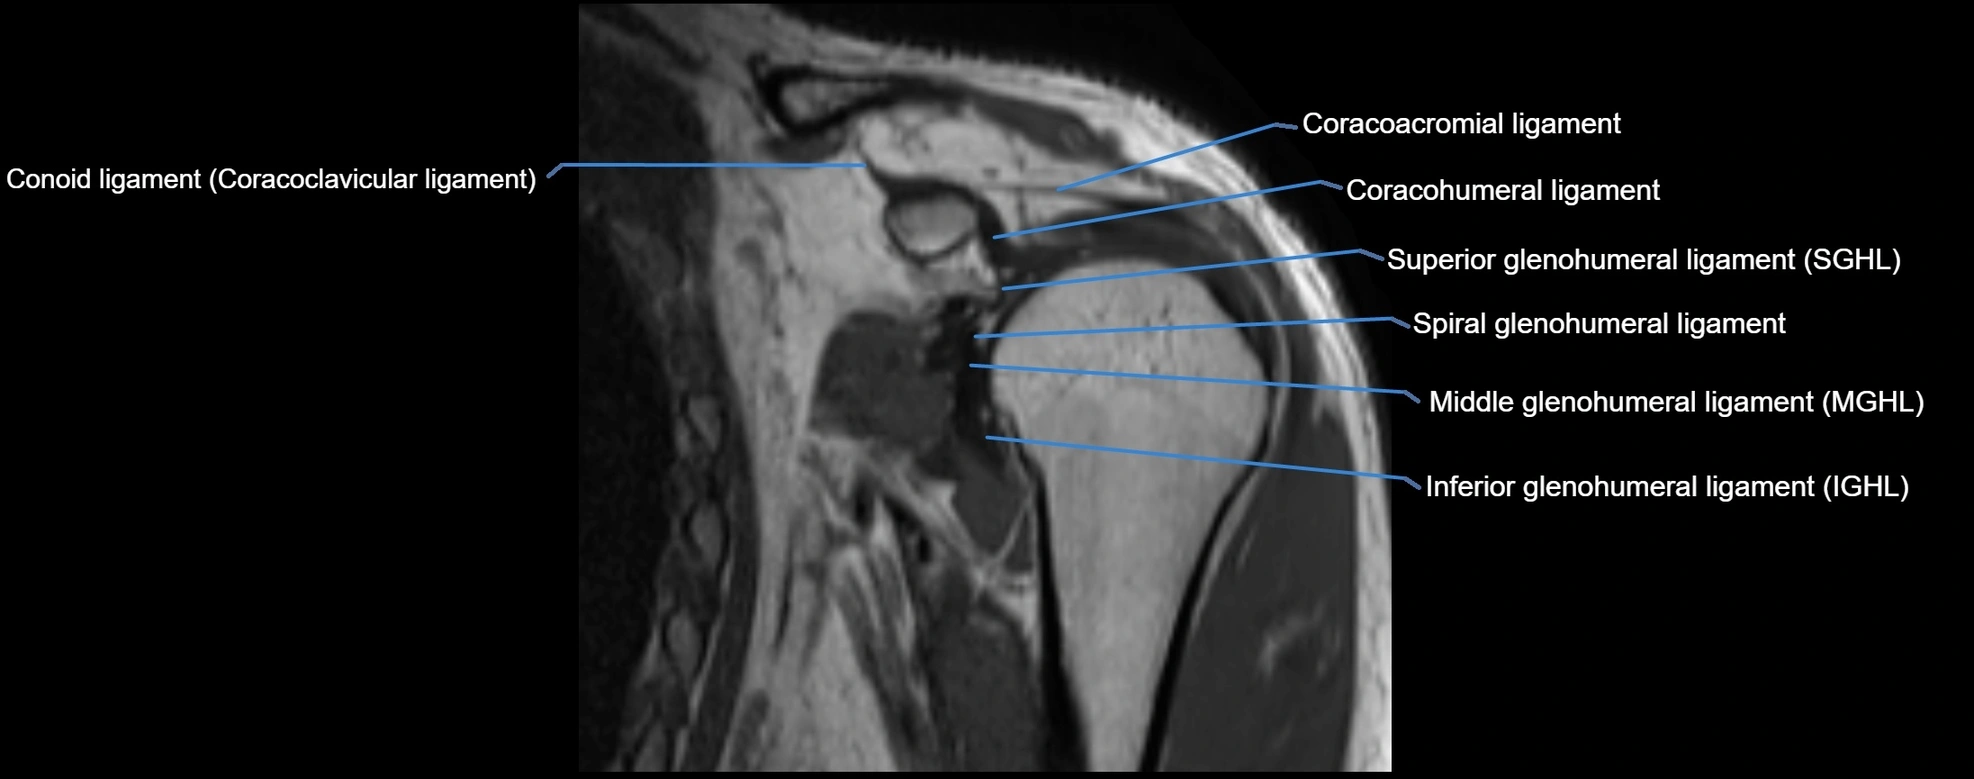

MRI Appearance

• T1-weighted images:

• Normal ligament: Low signal (dark linear band) spanning acromion to clavicle.

• Surrounding fat planes: Bright, delineating the ligament clearly.

• Marrow of clavicle and acromion: Bright due to fatty content.

• Tears: Discontinuity or irregular thickening with intermediate-to-bright signal.

• Chronic injury: Thinning, fraying, or irregular low-signal fibers with adjacent scarring.

• T2-weighted images:

• Normal ligament: Low signal, homogeneous.

• Partial tear or sprain: Focal hyperintensity or thickening.

• Complete tear: Discontinuity with fluid-bright gap between clavicle and acromion.

• Associated edema: Bright signal in distal clavicle or acromion marrow.

• STIR:

• Normal ligament: Dark linear band.

• Injury or inflammation: Bright hyperintense signal in and around ligament fibers.

• Highlights periligamentous soft-tissue edema, especially in acute trauma.

• Proton Density Fat-Saturated (PD FS):

• Normal ligament: Low signal, uniform thickness.

• Partial tear or sprain: Bright signal or contour irregularity.

• Complete tear: Clear discontinuity with bright signal gap and joint effusion.

• Excellent for assessing joint capsule, coracoclavicular ligaments, and periarticular edema.

MRI images

image